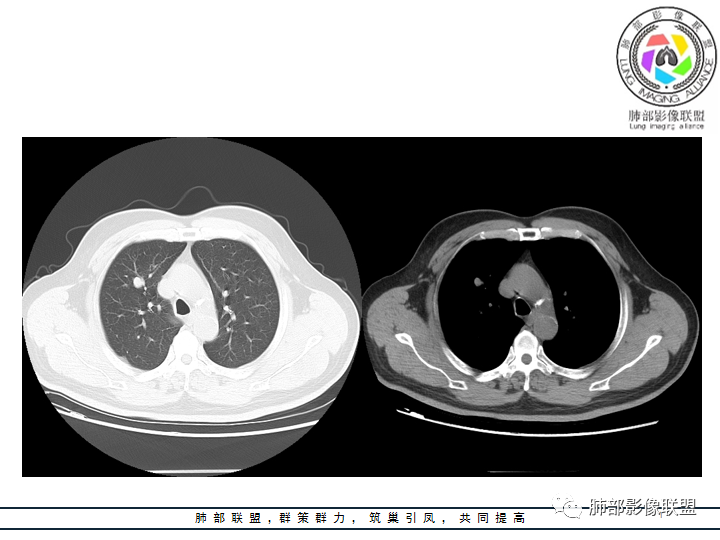

老年男性患者,长期吸烟史,没有呼吸系统临床表现。胸部CT示右肺上叶实性密度结节影,密度均匀,未见空洞及钙化,边缘较光整,未见分叶及毛刺。血管影旁现侧出,支气管进入并截断,不均匀强化。

蔡磊:右肺上叶实性结节,膨隆,收缩力弱,支气管近端有渐进性变窄,中等以上幅度强化,考虑神经内分泌癌,大?

万琦:看到有强化,错构瘤可能性小,感觉分支支气管有截断,大细胞需要考虑一下,类癌>PSP>大细胞,男性类癌发生率比较低。

王飞:这里可见支气管阻塞中断,神经内分泌能性大于PSP。